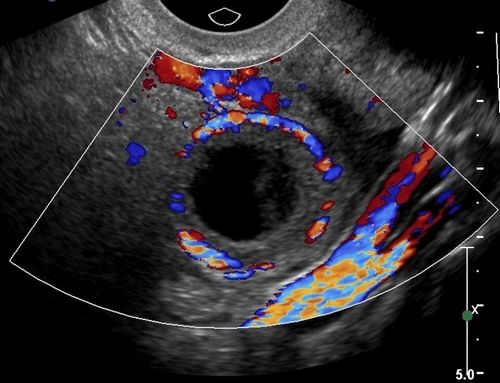

При дослідженні яєчників лікар спостерігає в одному з них жовте тіло, яке починає функціонувати з моменту овуляції і до появи плаценти, що відбувається приблизно на 10 тижні вагітності. Жовте тіло за своїми розмірами дуже вариабельно, в середньому буває 15-20 мм. Його ехогенність також може бути найрізноманітнішою, воно повинно добре постачається кров'ю при використанні методики КДК.

У даної пацієнтки 30 років при дослідженні в режимі доплерографії виявляється ефект посиленої васкуляризації (кровообігу) навколо жовтого тіла. Знімок зроблений в першому триместрі берменности.